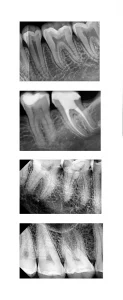

RVG provides high-resolution images, critical for accurate diagnosis and treatment planning. The clarity and detail offered surpass traditional X-ray films, allowing for better detection of dental conditions.